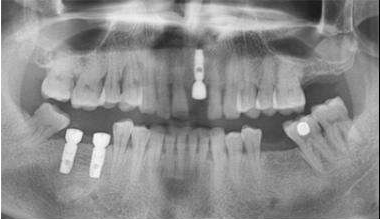

傳統(tǒng)種植牙通常需要4-6個(gè)月的愈合期,這對(duì)我們?nèi)粘I钪姓5难例X使用會(huì)帶來(lái)很大的影響,所以現(xiàn)在大部分有種植牙需要的患者都會(huì)選擇——負(fù)重種植牙。

今天我們就來(lái)了解一下“負(fù)重”種植牙技術(shù)負(fù)重種植牙就是指種植體在植入的同時(shí),馬上就以以安裝臨時(shí)義齒的行為;

負(fù)重種植牙有很多優(yōu)點(diǎn),但不是所有人都可以做的,需要經(jīng)過(guò)專業(yè)的檢測(cè)達(dá)標(biāo)后才可以進(jìn)行種植:1.患者骨密度質(zhì)量達(dá)到I、II、III號(hào)骨質(zhì)。

2.患者種植體植入的部位有達(dá)標(biāo)厚度的皮質(zhì)骨,且有足夠的健康附著牙齦;

3.患者的種植區(qū)域有可以滿足種植體植入后不會(huì)產(chǎn)生缺損的骨量;

4.患者的種植體的長(zhǎng)度在10毫米以上,直徑在3.5毫米以上。且可以采用表面經(jīng)過(guò)處理粗糙的階梯狀或者是螺旋狀的種植體。

CBCT拍攝,進(jìn)行牙槽骨厚度、寬度和高度的測(cè)量。